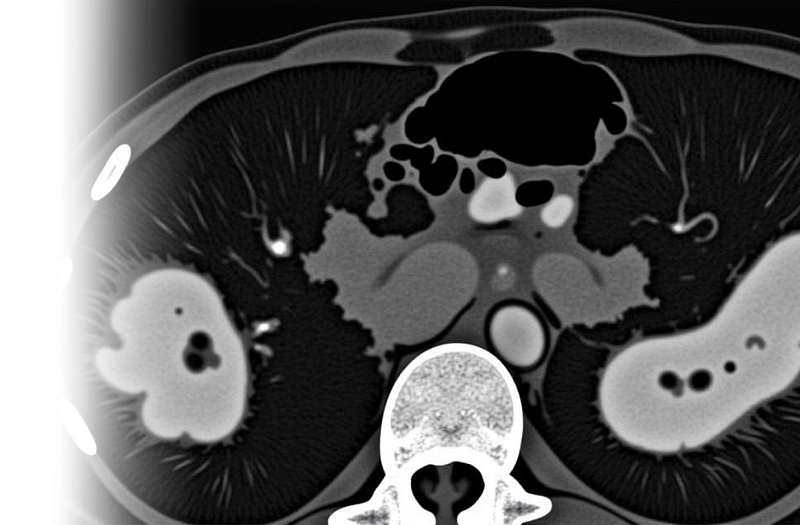

Компьютерная томография органов грудной клетки, брюшной полости и забрюшинного пространства с контрастированием – важный метод исследования органов грудной клетки, брюшной полости с внутривенным введением йодного контрастного препарата с помощью автоматического инжектора и с последующим пофазным сканированием.

Пациенту внутривенно вводится контрастное вещество, которое обеспечивает более качественную видимость органов на получаемых снимках, что позволяет выявить даже самые незначительные изменения в исследуемой области.

высококачественные снимки органов и тканей